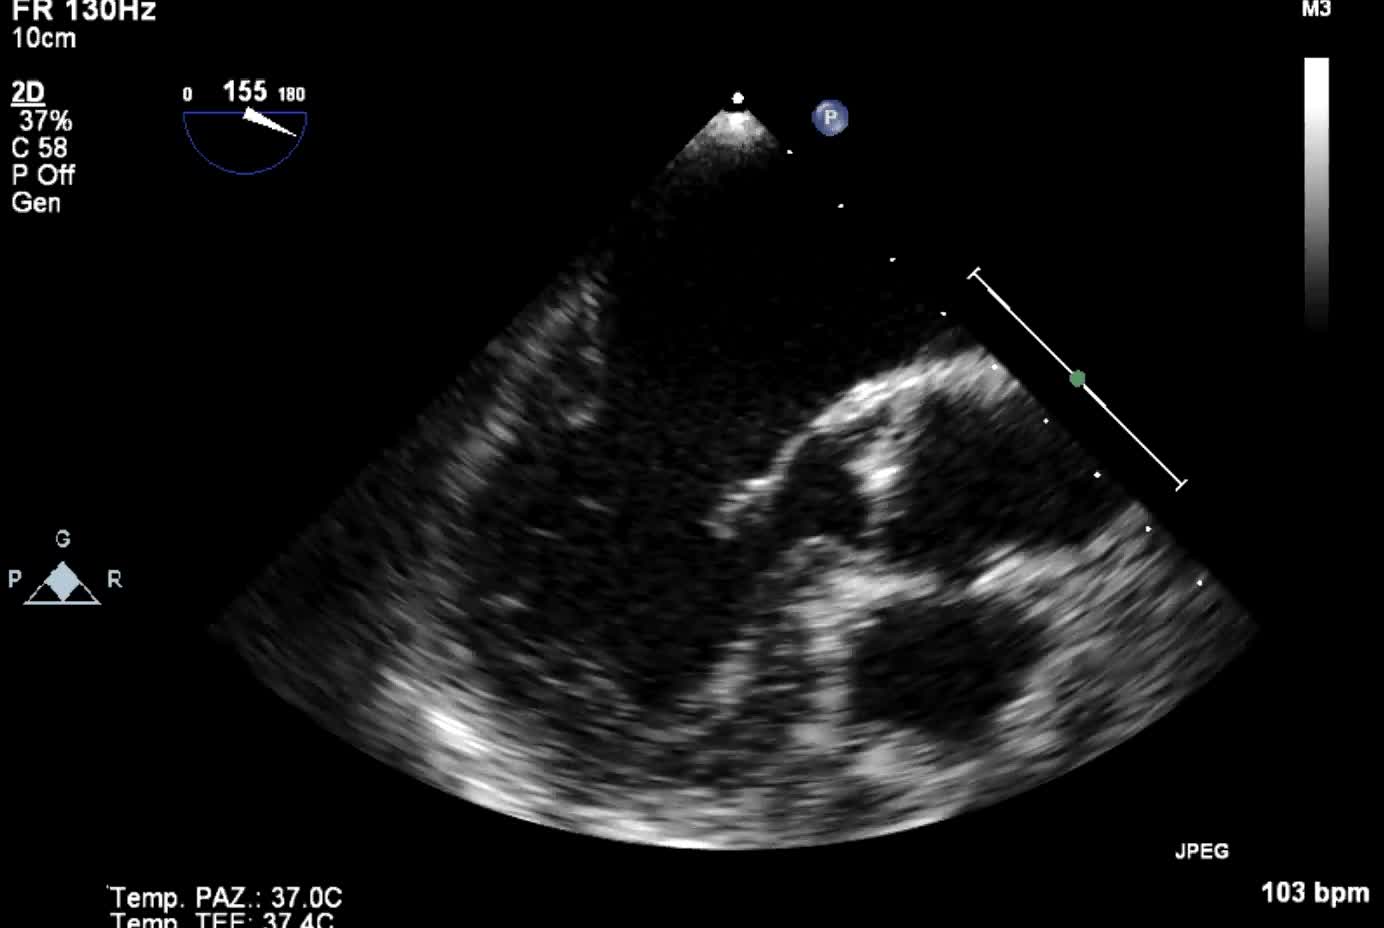

Titolo:

Insufficienza valvolare aortica acuta post-traumatica

Autore:

Andrea Barbieri